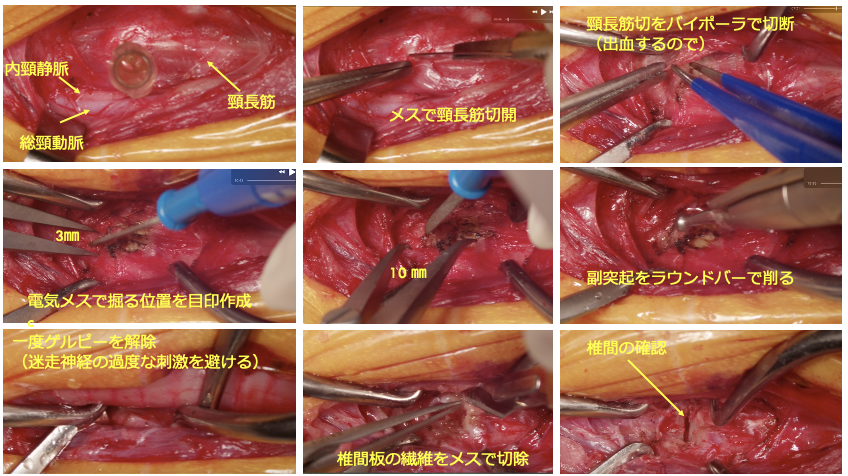

犬の頸部椎間板ヘルニアとは、頚椎と頚椎の間の椎間板が飛び出して、脊髄や神経を圧迫してしまう病気です。症状は、軽度な場合は首を動かすのを嫌がる、抱き上げるとキャンと鳴く、元気食欲低下などが認められます。中等度から重度になると、頸部の痛みが強くなり、ふらつき、四肢麻痺となり起立・歩行不能となります。診断には、CT・MRIが必要となります。軽度から中等度の場合は、内科的に治療することもありますが、重度の場合は、外科的介入が必要となります。外科的な方法としては、腹側スロット術(ベントラルスロット術)が一般的に行われます。椎間板ヘルニアが多発する場合は、背側椎弓切除術を行います。